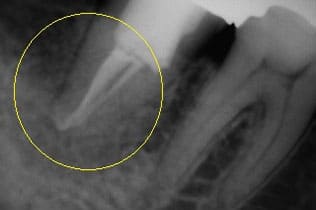

左側のレントゲン写真はリーマーが折れこみ、骨に刺さり、骨の中で膿の袋を作ってしまっている状態です。他の歯科医院さんから何度行っても摘出が出来なかったとの事で御依頼を頂きました。慎重にその折れこんだリーマーを除去し、根管治療を行い、最終的にMTAセメントという歯を修理するセメントで封鎖しました。